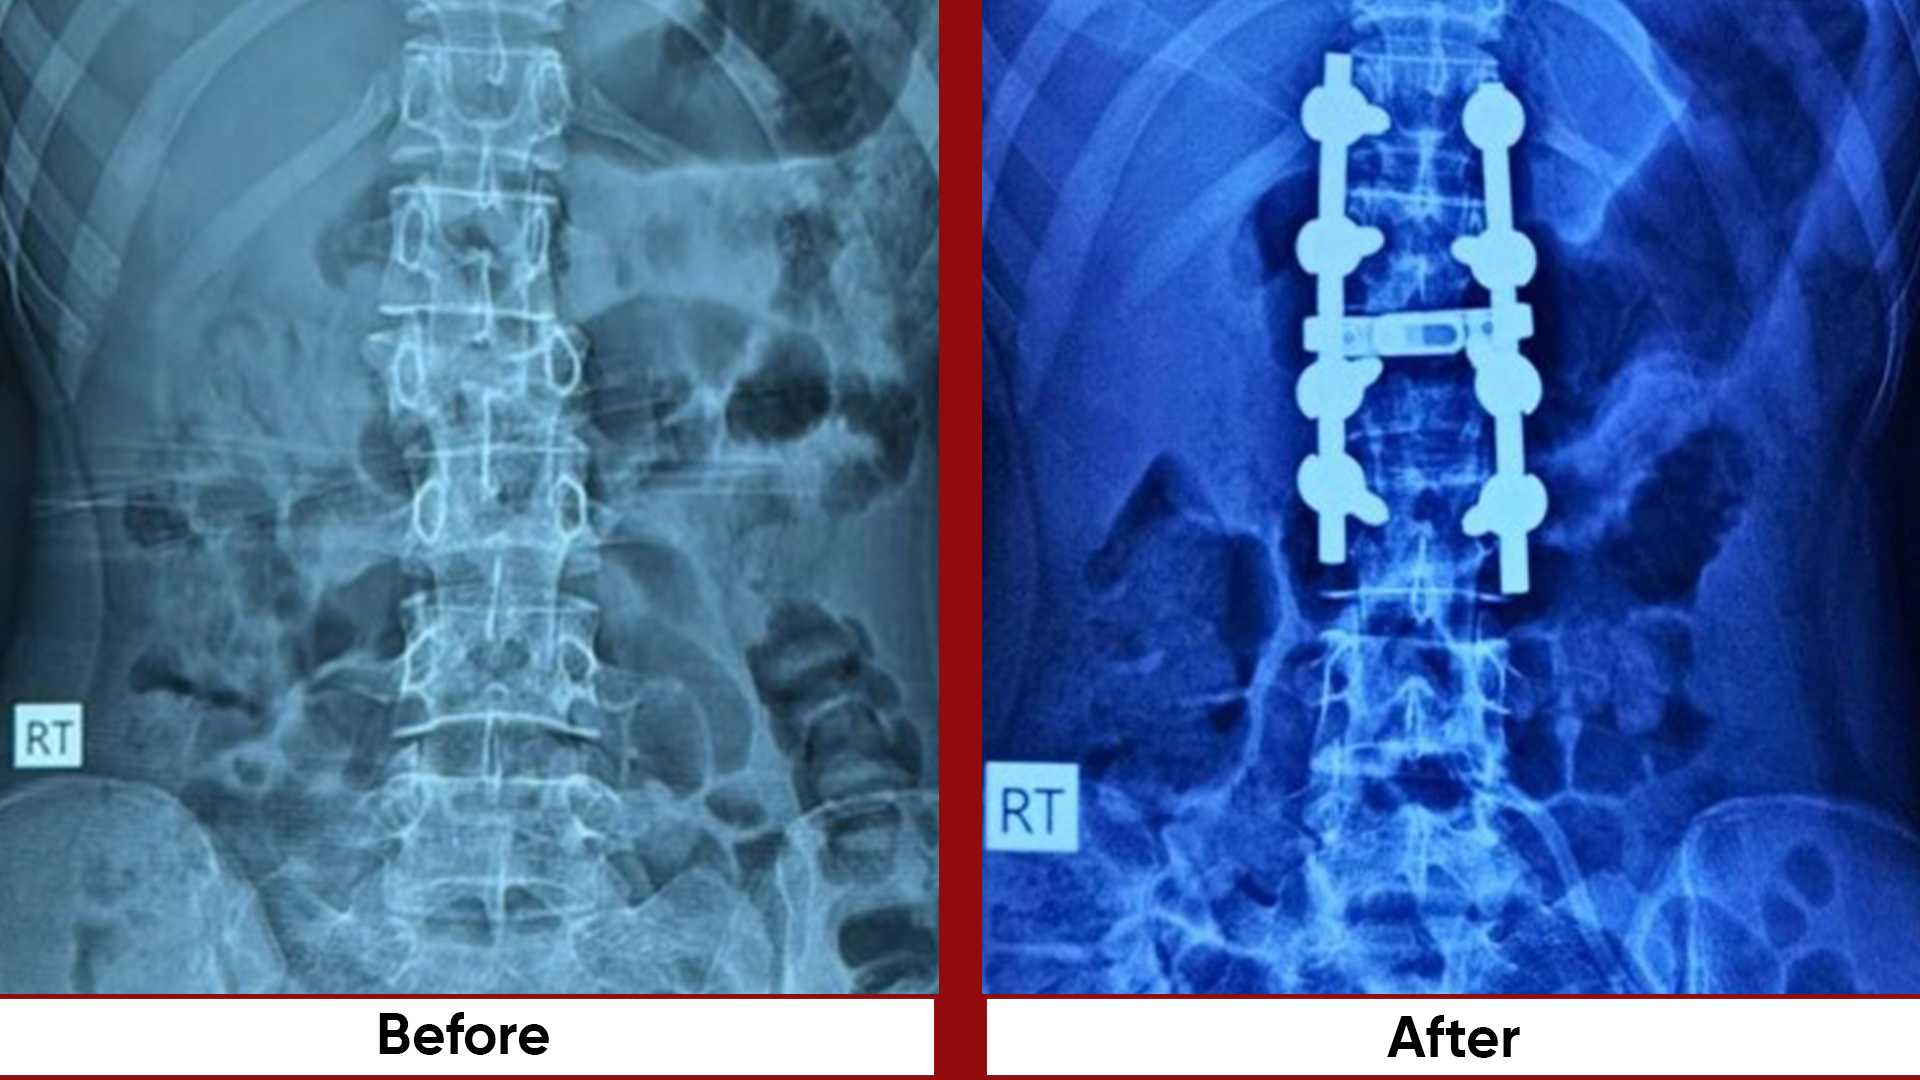

Procedures

• Fracture Management (simple and complex trauma)

• Pelvic & Acetabular Fracture Fixation